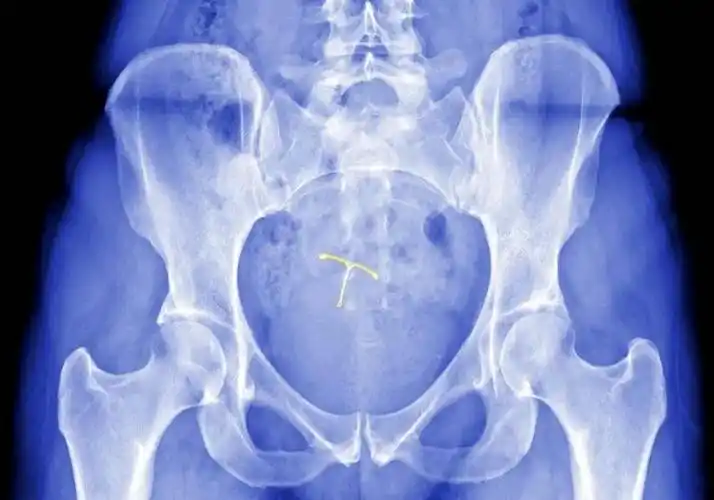

【女性健康】上节育环好吗?对子宫会有什么影响呢?